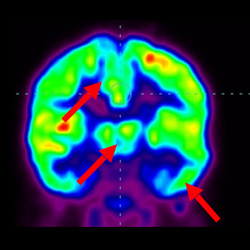

細(xì)胞治療前PET CT掃描顯示神經(jīng)組織中的藍(lán)/黑色區(qū)域,表明腦癱引起的大腦損傷。

腦癱細(xì)胞療法, 腦癱治療

細(xì)胞治療后,藍(lán)色和黑色區(qū)域減少,并且看到更活躍的區(qū)域。這表明損傷減少并改善了大腦功能。